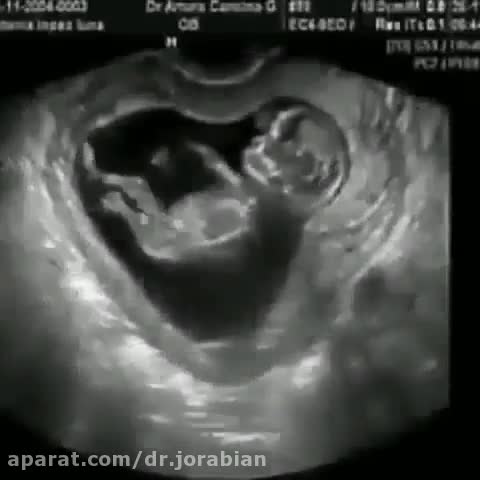

سونوگرافی دوران بارداری

دکتر مرتضی جورابیان مرکز رادیولوژی و سونوگرافی

در سونوگرافی دکتر جورابیان مجهز به دستگاه فیلیپس می باشد که انجام هر گونه سونوگرافی و رادیولوژی را آسان نموده است . صحبت های دکتر جورابیان متخصص رادیولوژی را در این باره بشنوید. برای کسب اطلاعات بیشتر به سونوگرافی دکتر مرتضی جورابیان در اهواز مراجعه نمایید. شماره تماس :25 70 33 33 -061 یا به آدرس سایت http://drjoorabian.ir/مراجعه کنید .